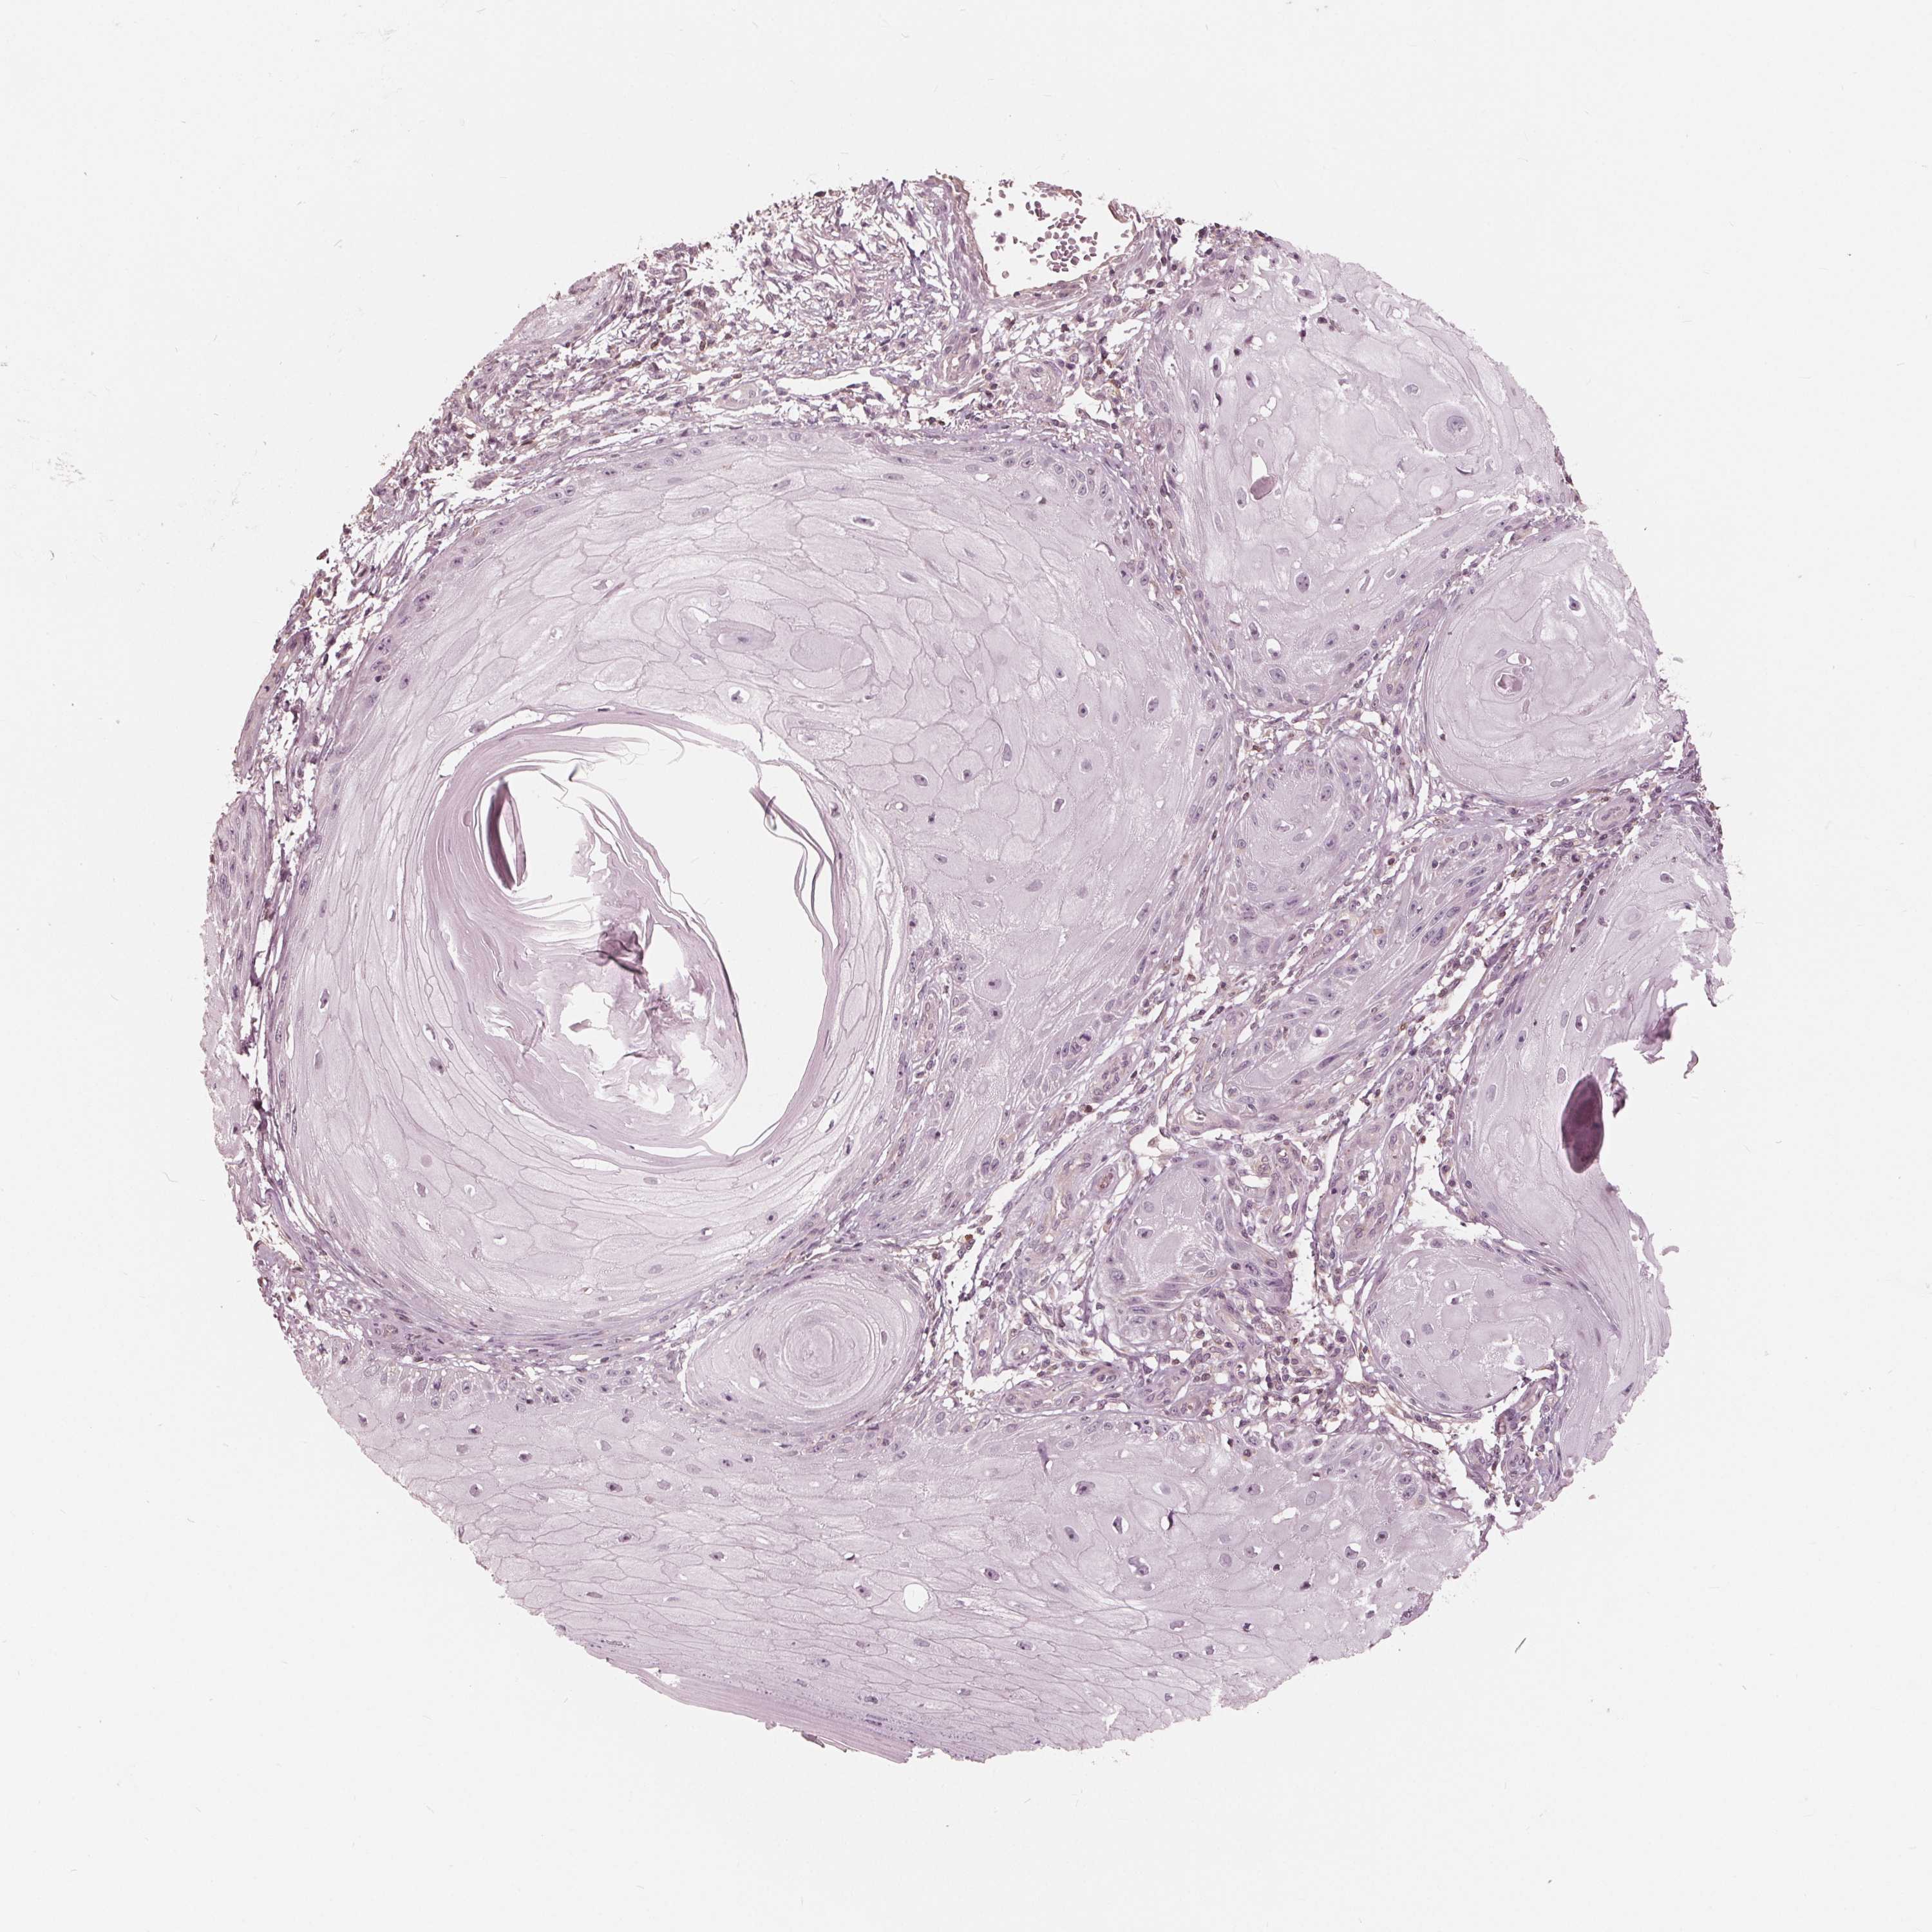

SKIN CANCER - Protein expressioni

A mouse-over function shows sample information and annotation data. Click on an image to view it in a full screen mode. Samples can be filtered based on level of antibody staining by selecting one or several of the following categories: high, medium, low and not detected. The assay and annotation is described here.

Antibody staining in the annotated cell types in the current human tissue is reported as not detected, low, medium, or high, based on conventional immunohistochemistry profiling in selected tissues. This score is based on the combination of the staining intensity and fraction of stained cells.

Each image is clickable and will lead to virtual microscopy that enables deeper exploration of all samples and also displays staining intensity scores, fraction scores and subcellular localization as well as patient and tissue information for each sample.

Antibody HPA067388

Intensity

Strong

Moderate

Weak

Negative

Quantity

>75%

75%-25%

<25%

None

Location

Nuclear

Cytoplasmic/membranous

Cytoplasmic/membranous,nuclear

Basal cell carcinoma

Squamous cell carcinoma, NOS